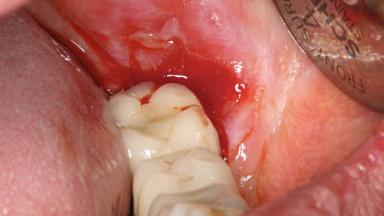

This case describes the ongoing management of a 64-year-old healthy, non-smoking female patient with erosive oral lichen planus (OLP) affecting the gingivae and the buccal and lingual mucosa. The peri-implant mucosa was also affected subsequent to implant placement. The patient had osseointegrated implants (four in the maxilla, four in the mandible) placed following extraction of hopeless teeth and a healing period. The patient had a history of OLP prior to implant placement and had been referred to an oral-medicine specialist for definitive diagnosis and treatment. She exhibited generalized oral mucosal involvement. Following a clinical assessment, biopsy, and blood tests, she was treated with topical corticosteroids. Systemic prednisolone was reserved for severe flare-ups. Amphotericin lozenges were used in combination with corticosteroid treatment to prevent the development of oral candidiasis.